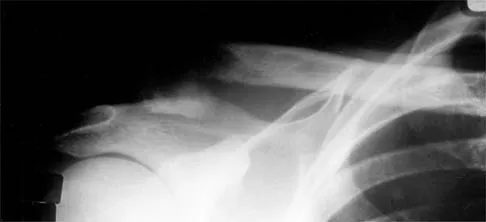

After closed reduction of the dislocation shown in Figure 42, it is essential to avoid placing the upper extremity in what position for the first 4 to 6 weeks?

Explanation